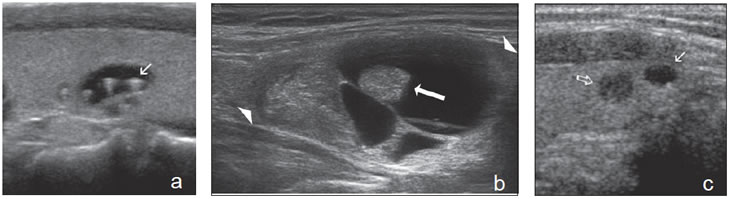

Un nódulo coloideo mixto puede aparecer como un quiste con un nódulo mural isoecogénico, excéntrico, que protruye hacia el lumen simulando una formación papilar, habitualmente vascularizado, que no corresponde a tejido neoplásico (Figura 19a). Si el componente sólido está rodeado por fluido, separado de la pared, y además tiene focos hiperecogénicos, es más difícil confundirlo con un tumor quístico (Figura 19b y c).

Figura 19. a) Nódulo coloideo, que muestra

una proyección de aspecto papilar hacia

el lumen, que corresponde a tejido no

neoplásico, igualmente vascularizado que

el resto del componente sólido del nódulo

(flecha abierta); b) y c) Nódulo coloideo,

predominantemente quístico, con componente

sólido (flecha), que muestra una forma

vegetante completamente rodeada de

coloide, con dos focos puntiformes en el

área más central.